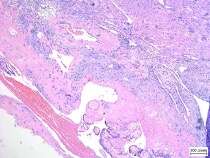

This is a case report of a 35-year-old G2P0 (0020) who presented with persistent vaginal bleeding after completion curettage for an incomplete abortion. Transvaginal sonography showed an endometrial echogenic mass with cystic spaces with abundant color flow, and beta‐human chorionic gonadotropin had decreasing trends. Assessment was postpartum hemorrhage secondary to retained secundines and multiple myoma uteri. On hysteroscopic resection of the retained secundines, profuse bleeding led to hemorrhagic shock. Hence, hysterectomy was performed. Histopathology showed placenta accreta.

Persistent bleeding post-completion curettage and increased vascularity on ultrasound should lead to a high suspicion of placenta accreta in the first trimester. This case highlights the possibility of placenta accreta in the first trimester and the need for a diagnostic consensus for its detection. Prompt diagnosis is essential for timely intervention and proper patient counseling, including the possibility of hysterectomy if all other conservative methods fail.